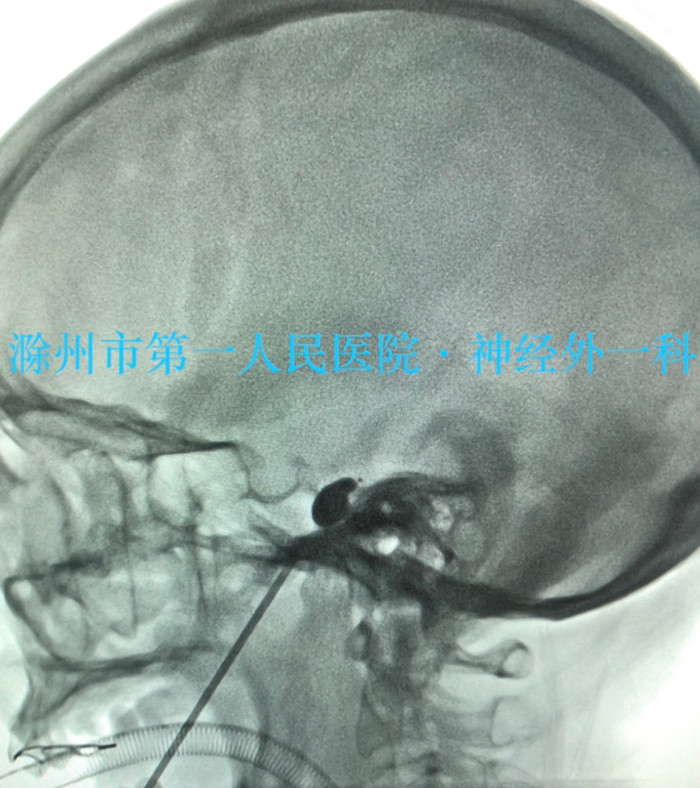

News近日,我院神经外科一病区成功开展一例“经皮三叉神经半月神经节球囊压迫术(PBC)”手术,为患者解除了病痛。

患者沈女士,56岁,先天性聋哑合并三叉神经痛。早期出现阵发性左下颌磨牙处刀割样疼痛症状时,患者考虑是牙痛引起的现象,多次在外院就诊治疗,在拔除疼痛相关区域的牙齿后症状仍得不到缓解,后就诊于我院神经内科,最终确定为三叉神经痛。为该患者完善术前评估后,主治医师多次与患者家属沟通,最终确定进行风险相对较小的“经皮三叉神经半月神经节球囊压迫术(PBC)”手术。手术从疼痛侧口角外侧(经典Hartel路径)用穿刺针进行穿刺,穿刺到位后通过穿刺针植入微球囊对三叉神经半月节进行压迫,仅仅2~3分钟即结束手术,手术顺利,术后患者恢复良好。